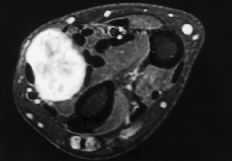

Había 55 tumores derivados de los vasos, de los que 34 eran hemangiomas (20 cavernosos, nueve venosos, tres endoteliales y dos capilares), 12 tumores glómicos, seis leiomiomas, dos fístulas arteriovenosas y un linfangioma. Treinta y siete eran mujeres y 18 hombres, siendo la edad media de 45 ± 15 años (máximo: 73 y mínimo: 8 años). La distribución por edades de los diferentes subtipos histológicos fue extremadamente dispersa. La localización más frecuente fueron los dedos (31 casos), seguido de la palma y eminencias (14 casos) y muñeca y dorso de la mano (5 casos de cada localización). Diez de los tumores glómicos afectaban a mujeres y siete de ellos eran de localización subungueal (Fig. 2).

En los hemangiomas cavernosos fue frecuente el hallazgo de calcificaciones intravasculares, en ocasiones visibles radiográficamente. La RM fue específica, existiendo un patrón homogéneo de alta intensidad en relación con su contenido hemático estático (Fig. 3).

Los tumores vasculares aparecen con mayor frecuencia en la cabeza y cuello, aunque un 20% puede aparecer en las extremidades, y de ellos el 50% lo hace en las superiores.6,15,19,20 Según Myhre-Jensen23 los tumores de estirpe vascular es la tercera tumoración en frecuencia de una serie de 1.331 casos, de entre los cuales la localización en la mano o la muñeca supuso el 20%. Representan el 10% de los tumores de partes blandas de la mano.2,5,6,14,20,25,26,34,38 Hemos diagnosticado 55 casos, lo que significa un porcentaje algo más elevado que las series consultadas. El tipo histológico más frecuente ha sido el hemangioma cavernoso(20 casos). Se distingue por la formación de grandes canales vasculares mezclados con capilares de tamaño normal. En ellos es frecuente la formación de flebolitos en relación con el remanso vascular, pudiéndose observar en la radiología convencional.2,6,17,20,22,24-27,38 Los estudios de RM se caracterizan por un patrón homogéneo e hiperintenso en las secuencias T2 (Fig. 3). A veces dan imágenes serpenteantes en relación con los canales vasculares y los espacios entre ellos.17,29

Figura 3. Hemangioma que engloba los tendones flexores del dedo anular. Corte transversal en la palma de la mano, donde se constata un patrón homogéneo de alta intensidad de señal de resonancia (T1 potenciada).